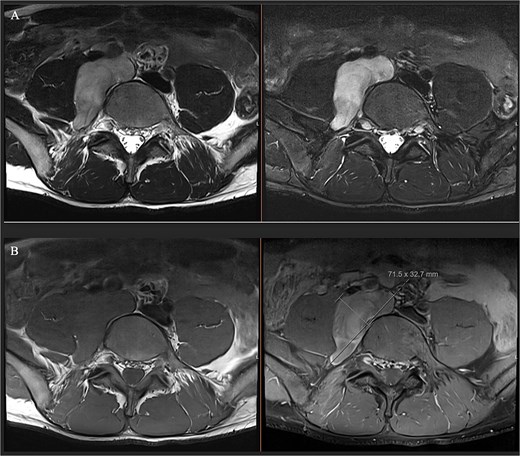

A male in their early twenties presented with a 4-year history of a multitude of symptoms including bone and joint pains in his chest, abdomen and lesser right hip pain. He was seen by an osteopathy and physiotherapist and then referred to a GP who performed plain x-rays of bilateral hips and an abdominal ultrasound, which were normal. His symptoms persisted, and back MRI showed a lobulated mass in the right paraspinal region extending from the L4-L5 to the L5-S1 level, medial to the psoas muscle (Fig. 1), displacing the iliac vessels anteriorly and psoas laterally without involvement of exiting nerves or lumbar plexus (Fig. 2).

(A) Axial T1 MRI: Left) pre-contrast, right) post contrast demonstrating mild contrast enhancement. (B) Axial T2 MRI: Left) axial T2, right) axial T2 with fat saturation showing hypertense lesion displacing iliac vessels and psoas.

Ganglioneuroma was the principal differential. Bloods results were reassuring against a malignant neuroblastic, mixed germ cell tumour or lymphoma. MRI demonstrated common features suggestive but not exclusive to ganglioneuroma including T1 hypointensity and T2 hyperintensity, and mild contrast enhancement [5] (Figs 1 and 2). Differentials included a nerve sheath tumour however there was no definitive associated exiting nerve or lumbar plexus involvement on MRI. Minimal glucose avidity on PET also pointed towards a benign process. The histopathological findings of mature ganglion cells mixed with Schwan cells are the hallmark of ganglioneuroma and important for distinguishing this benign tumour from neural crest derived tumours [8].